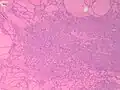

Fine-needle aspiration for cytology is generally not indicated in an autonomously functioning thyroid nodule, as the risk of malignancy is low, and it is generally difficult to distinguishing between a benign lesion and a malignant lesion in such specimens.[8] If thyroidectomy is performed, histopathology can corroborate the diagnosis. Toxic multinodular goiter more or less corresponds to diffuse or multinodular hyperplasia of the thyroid (Grave's disease also shows hyperplasia, but typically more prominent thickening of follicular linings):

Various forms of degeneration are typically seen, with various forms pictured.